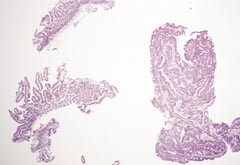

Pasient 4. En tre år gammel jente ble laserbehandlet for perianale vorter som ble oppfattet som kondylomer. Histologisk undersøkelse viste papillomatøs plateepitelhyperplasi med hyperkeratose (fig 8). Lysmikroskopisk var det ikke mulig å påvise noen HPV-forandringer. Eldre kondylomer kan mangle koilocytose og flerkjernede celler, som er typiske for en HPV-infeksjon. Biopsimaterialet ble derfor undersøkt med PCR med både konsensusprimere (16) og typespesifikke primere (17). HPV-DNA-type 6 ble påvist (fig 9). HPV 6 hører til de ikke-onkogene HPV-typer og finnes i kondylomer og lavgradige intraepiteliale neoplasier. Med PCR-teknikk fikk man bekreftet den kliniske diagnosen og at barnet var blitt adekvat behandlet.

Figur 8   Lysmikroskopisk bilde av perianal polypp fra pasient 4. Papillomatøs plateepitelhyperplasi med hyperkeratose. HPV-forandringer mangler